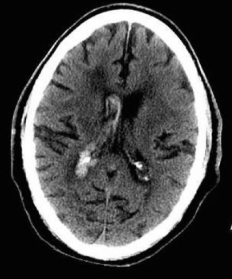

What is Intraventricular haemorrhage, and what does it look like on CT head?

Intraventricular haemorrhage: Blood collection in ventricles

CT finding: Hyperdense lesion in ventricle